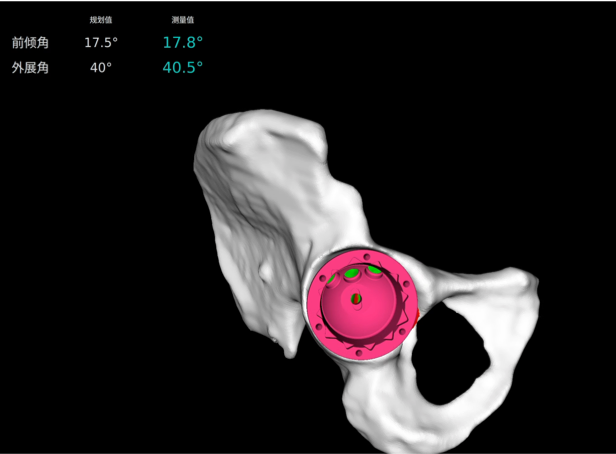

· 個(gè)性化規(guī)劃假體尺寸及安裝角度,預(yù)估安裝效果。

· 融合 CT 和 3D 模型,直觀顯示假體植入效果。

· 精準(zhǔn)高效執(zhí)行手術(shù)操作,實(shí)時(shí)安裝角度顯示,誤差控制在1°以內(nèi)。